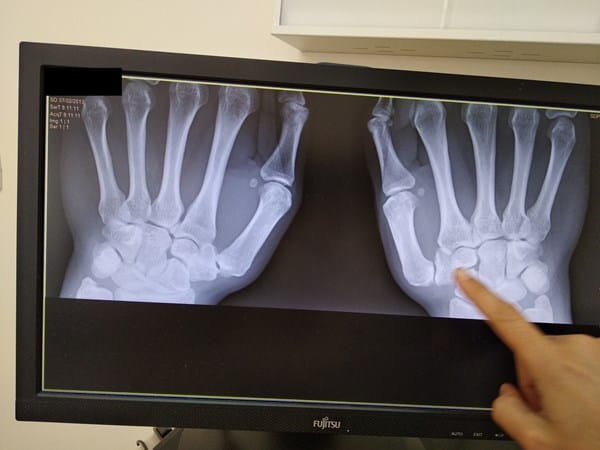

Les adjunto 2 radiografías actuales.

Y yo me pregunto, desde mi total ignorancia en la materia: ¿No se podría colocar el trapecio en una posición correcta? O bien, ¿sustituirlo completamente por una protestis?